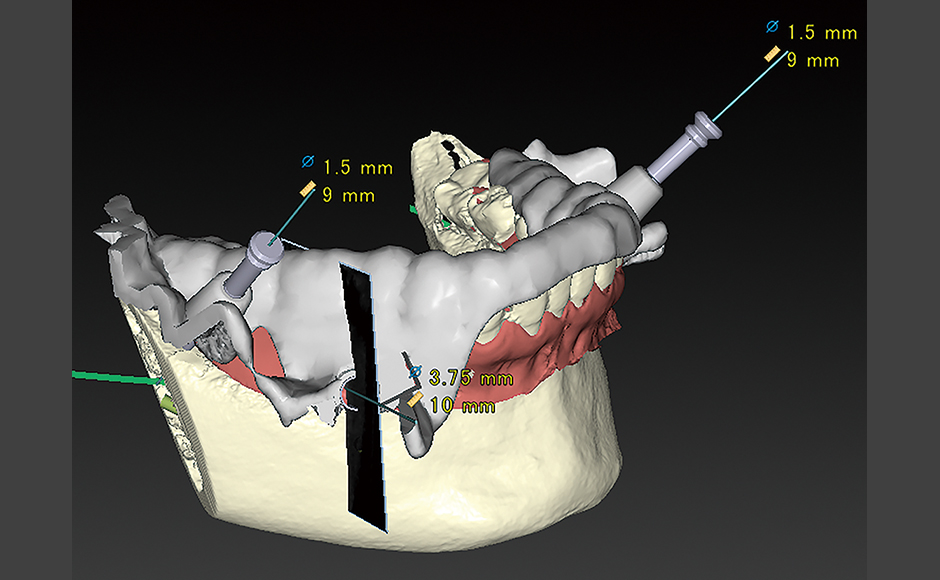

症例.1:穿孔を伴う根尖性歯周炎に対して非外科的歯内療法を行った症例

症例.2:外科的歯内療法を併用して根尖性歯周炎の治療を行った症例